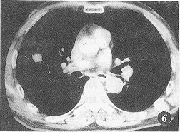

图6 右中肺低分化腺癌。瘤体内可见棘状突起征,PCNA表达面积为12423.25 μm2

CT征象分叶征的形成与肿瘤各部份生长速度不均匀和肺支架结构的制约有关(图5)。本组资料有深分叶征者的PCNA表达面积明显高于无深分叶征者,深分叶征的出现是癌细胞增殖活跃明显的表现。以往影像一病理对照研究发现,CT图像瘤肺交界面的恶性征象包括棘状突起与毛刺征。棘状突起是在分叶基础上部分分化程度低,生长更快的肿瘤细胞亚群沿血管、支气管周围的结缔组织内浸润或沿淋巴管内蔓延导致肿瘤形态不均(图6)。有棘状突起的瘤体PCNA表达面积明显高于无棘状突起者,进一步证实了有棘状突起肿瘤的恶性生物学行为。而毛刺征的形成部分可能也为浸润生长所致,但主要是间质反应的表现[10]。本组资料显示有毛刺征者的PCNA表达面积与无毛刺征者之间无显著性差异(P>0.05),表明判断周围型肺癌浸润潜能、恶性度和预后方面,棘状突起价值较大。